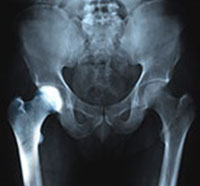

Osteoarthritis also called degenerative joint disease is the most common form of arthritis. It occurs most often in older people. This disease affects the tissue covering the ends of bones in a joint (cartilage). In a person with osteoarthritis, the cartilage becomes damaged and worn out causing pain, swelling, stiffness and restricted movement in the affected joint.

Inflammation of the joints is referred to as arthritis. The inflammation arises when the smooth covering (cartilage) at the end surfaces of the bones wears away. In some cases, the inflammation is caused when the lining of the joint becomes inflamed as part of an underlying systemic disease.